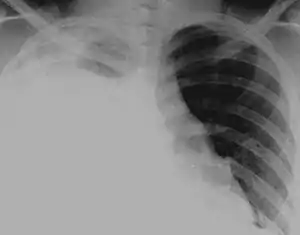

Hydrothorax

Hydrothorax is a type of pleural effusion in which transudate accumulates in the pleural cavity. This condition is most likely to develop secondary to congestive heart failure, following an increase in hydrostatic pressure within the lungs. More rarely, hydrothorax can develop in 10% of patients with ascites which is called hepatic hydrothorax. It is often difficult to manage in end-stage liver failure and often fails to respond to therapy.